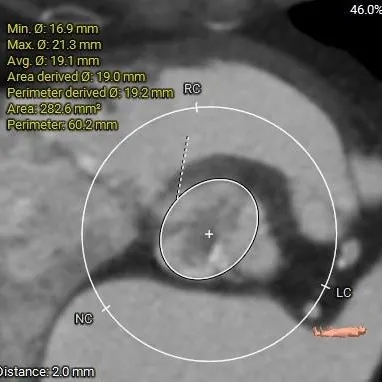

ANNULUS

周长63.6mm

周长径20.2mm

周长61.9mm

周长径19.7mm

周长62.0mm

周长60.2mm

周长径19.2mm